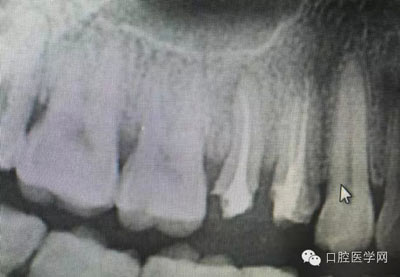

這是一例外院樹脂修復后十個月出現(xiàn)牙髓炎癥狀的患者。遇到這樣子的患者大家會怎么做,證明選擇,還有就是可做可不做治療的如何去平衡。

根管治療,我們在大學的時候就學習的東西,標準就在那里放著,可是很多時候我們熟視無睹,放任我們的想象去做。我們多些重視,多些心思,會好很多,認真對待每顆牙齒。